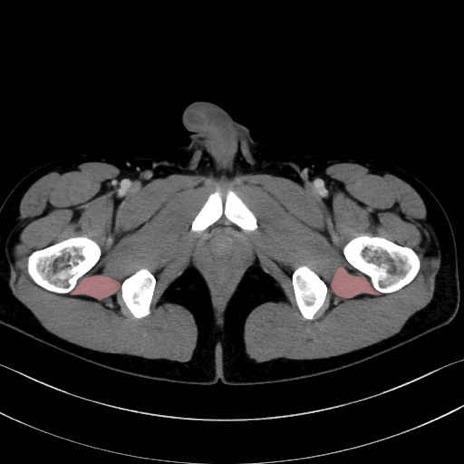

大腿方形筋 (Quadratus femoris)